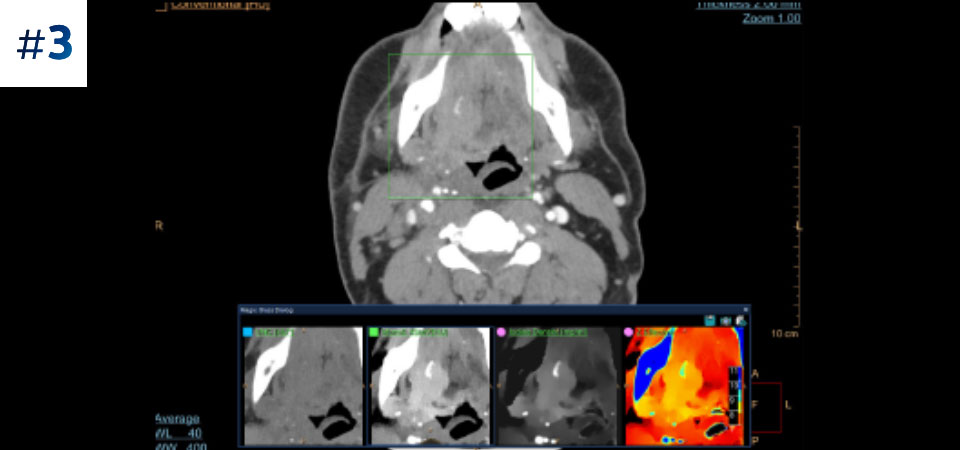

With detector-based spectral, you acquire multiple layers of data—conventional and spectral—within a single exposure and without special scan modes for improved tissue characterization and visualization.

Scan as usual A single scan for fast, low-dose conventional and spectral data for every patient, every time.

Always available 100% spectral, 100% of the time for results that are always available on-demand, even retrospectively.

Reduced follow-up exams Improved tissue characterization and visualization may reduce the need for follow-up scanning for sub-optimal exams and incidental findings.

Across patient types Benefits a wide range of patient types from pediatric to bariatric.